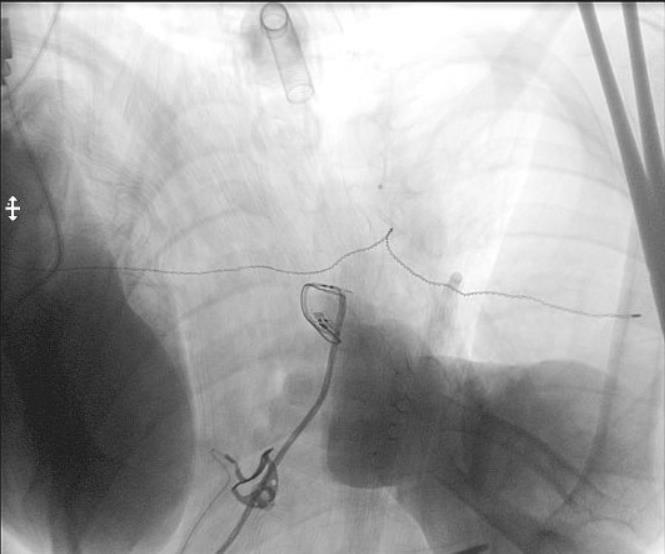

SDR involves surgically accessing the spinal cord (typically in the lumbosacral region, L2 to S1 or S2).The dorsal (sensory) nerve roots are carefully identified and then divided into smaller bundles called rootlets.

• Hydrophilic drugDaily dose 60-120mgSide effects at low plasma levelsBBB blocks passage (30-60mg oral = 12–

96 mg/ml CSF)Response to oral therapy not predictive

• High CSF concentration (501500 mcg/day = 30-1240 ng/ml CSF)Steady state in 24-48hLow plasma levels (5 ng/ml)Half-life

180 minutesHigher concentration at lumbar level (lumbar:cisterna magna = 4:1)Effective dose 100-1000 times lower

T10–12 spastic diplegia

C5–T2 spastic quadriplegia

C1–C4 secondary generalized dystonia